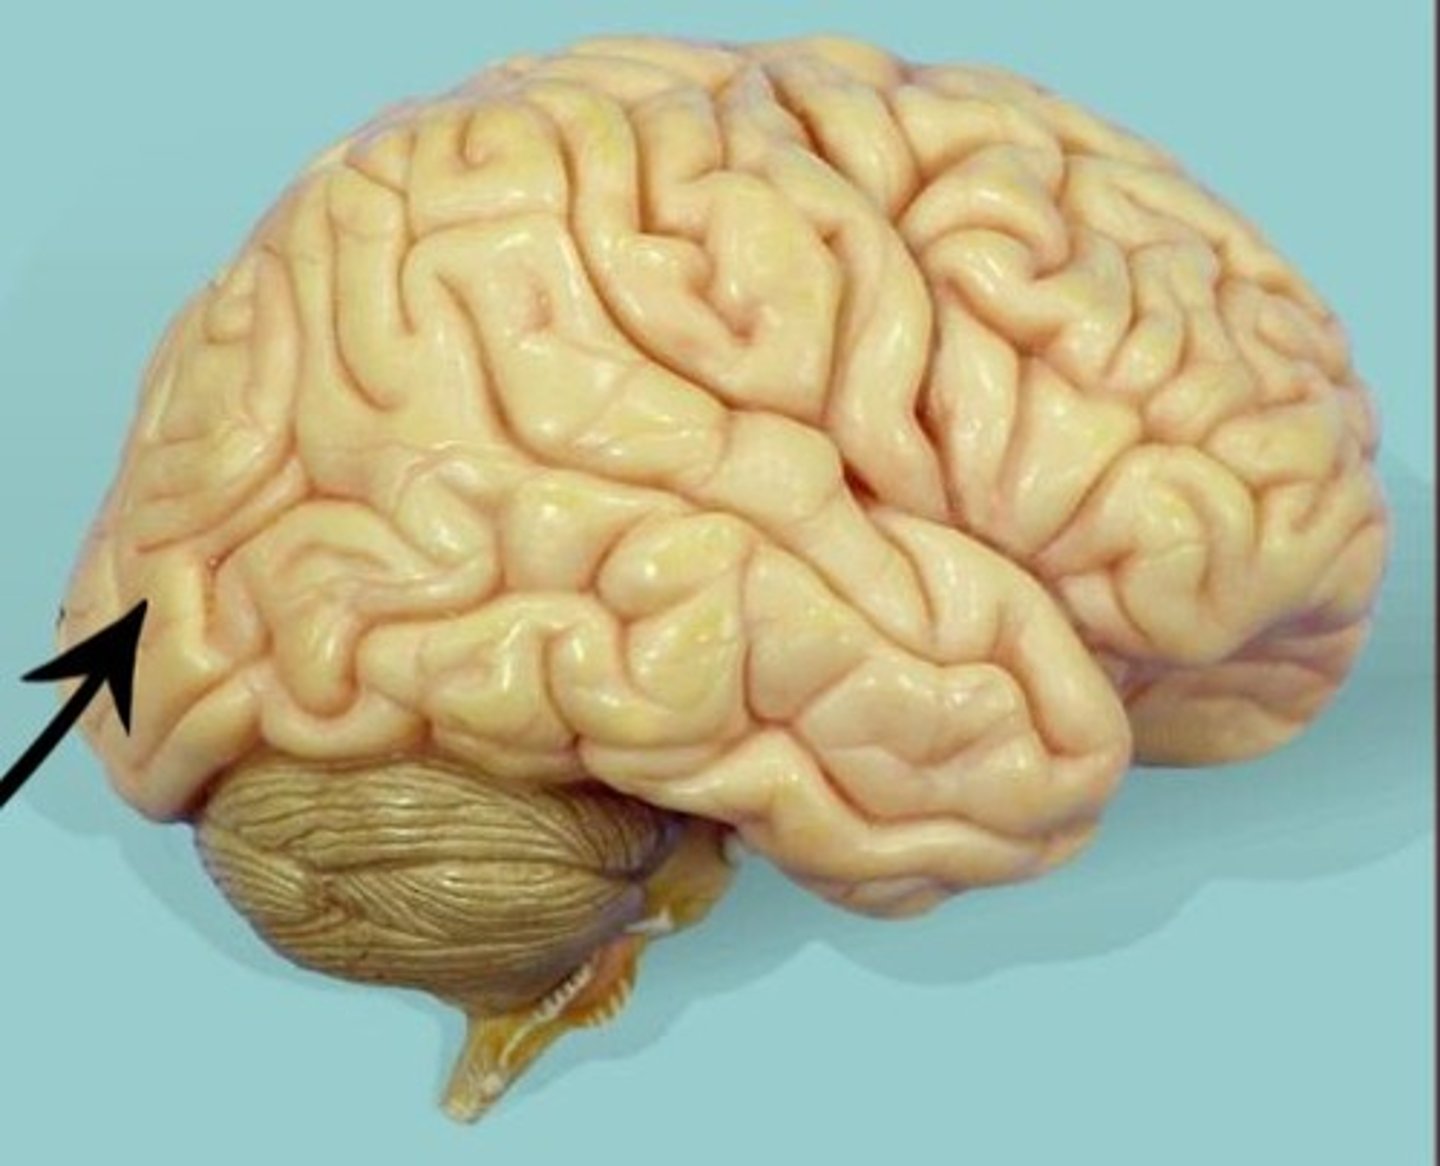

occipital lobe